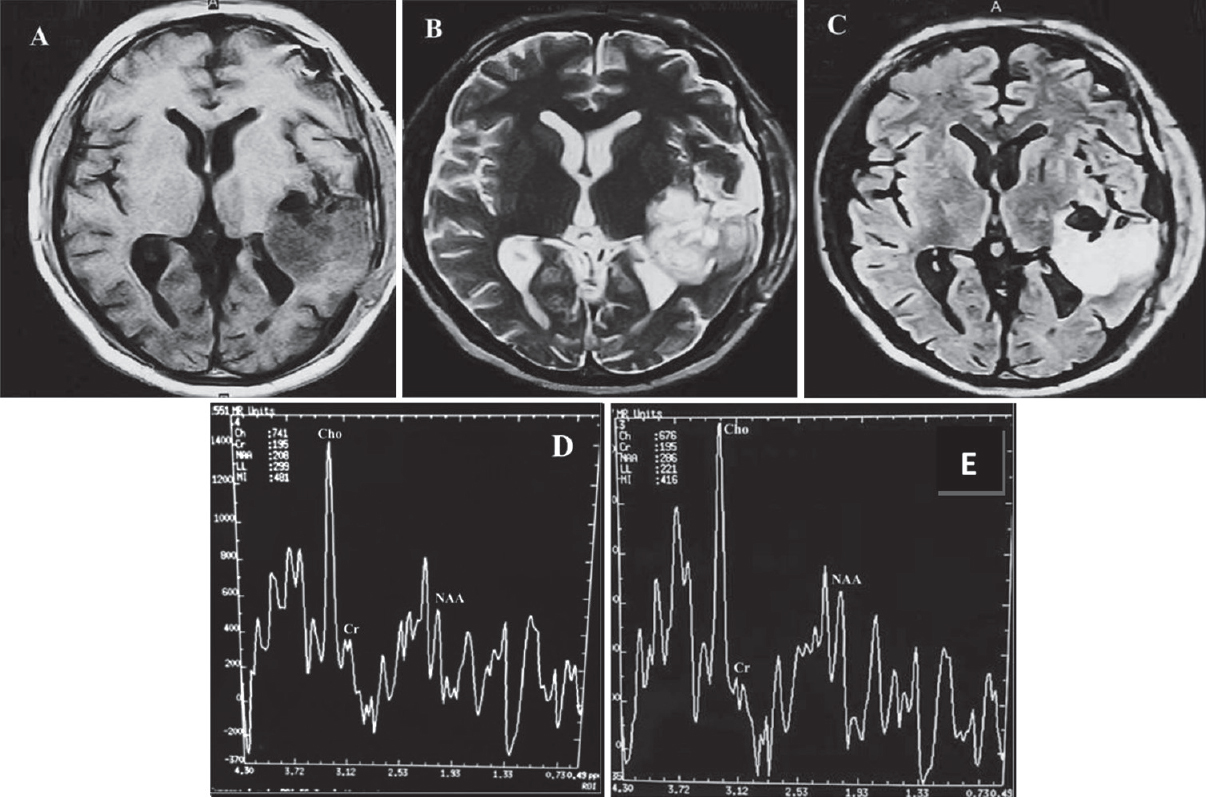

图3:按MRS评价的占位性病变组